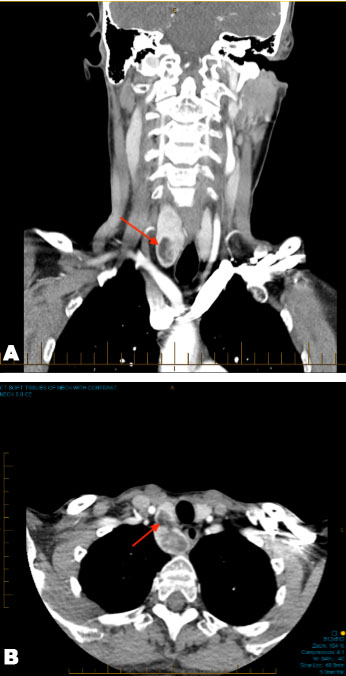

A 58-year-old asymptomatic Caucasian female was referred to the General Surgery clinic for review of two non-tender right-sided thyroid nodules, of unknown duration, which were incidentally discovered on plain film spine X-ray following a spinal fracture. Computed tomography (CT) of the neck demonstrated a goitrous nodule within the right lobe of the thyroid with no retrosternal extension, but with impingement and mild displacement of the trachea and esophagus (Figure 1). The patient had no history of thyroid disorders or irradiation, no significant family history of thyroid cancer or disease, and no history of autoimmune disease. Physical examination demonstrated a mildly enlarged thyroid with no palpable nodules, negative for Pemberton’s sign, without palpable cervical lymphadenopathy, and normal laryngeal motility.

Figure 1: (A) CT neck and chest demonstrating a goitrous nodule (see red arrow) in the right hemithyroid with mild displacement of the trachea and esophagus in coronal view. (B) CT neck and chest demonstrating a goitrous nodule (see red arrow) in the right hemithyroid with mild displacement of the trachea and esophagus in axial view.